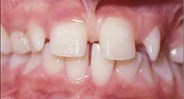

Photographs

side front front smile

Lateral Portrait Frontal Portrait Frontal Portrait Smile

front view left buccal maxillary mandibular

Right Buccal View Frontal View Left Buccal View Maxillary View Mandibular View